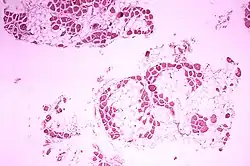

Myoblasts (cells with a single nucleus, represented in violet) fusing together to form muscle fibers (multinucleated muscle cells) during myogenesis